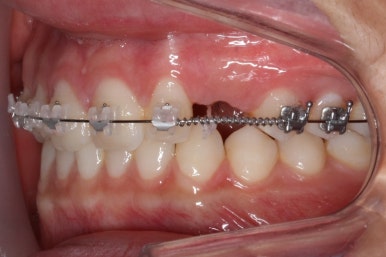

조금 더 위치가 바뀌었습니다.

송곳니 머리도 조금 보이는 것 같네요, 매우 섬세한 컨트롤이 필요하기 때문에 철사의 형태나 당기는 방향 등 조절을 잘 해줘야 합니다.

드디어 모습을 드러냈습니다.

마찬가지로 위치나 방향 등에 따라 정교하게 조절을 해줍니다.

부산매복치아교정 한 지 15개월만에 거의 제위치를 찾아가고 있는 모습입니다.

이번에도 매우 섬세한 조절을 위해 송곳니에는 철사가 두 줄로 연결되어 있기도 합니다.

어금니에는 일시적으로 치아를 띄워주기 위해 바이트레진이라는 것을 올리게 됩니다.

치아를 띄워주지 않으면 안쪽에 있던 송곳니를 바깥으로 데리고 나올 때 걸려서 못나오는 상황이 생길 수도 있기 때문입니다.